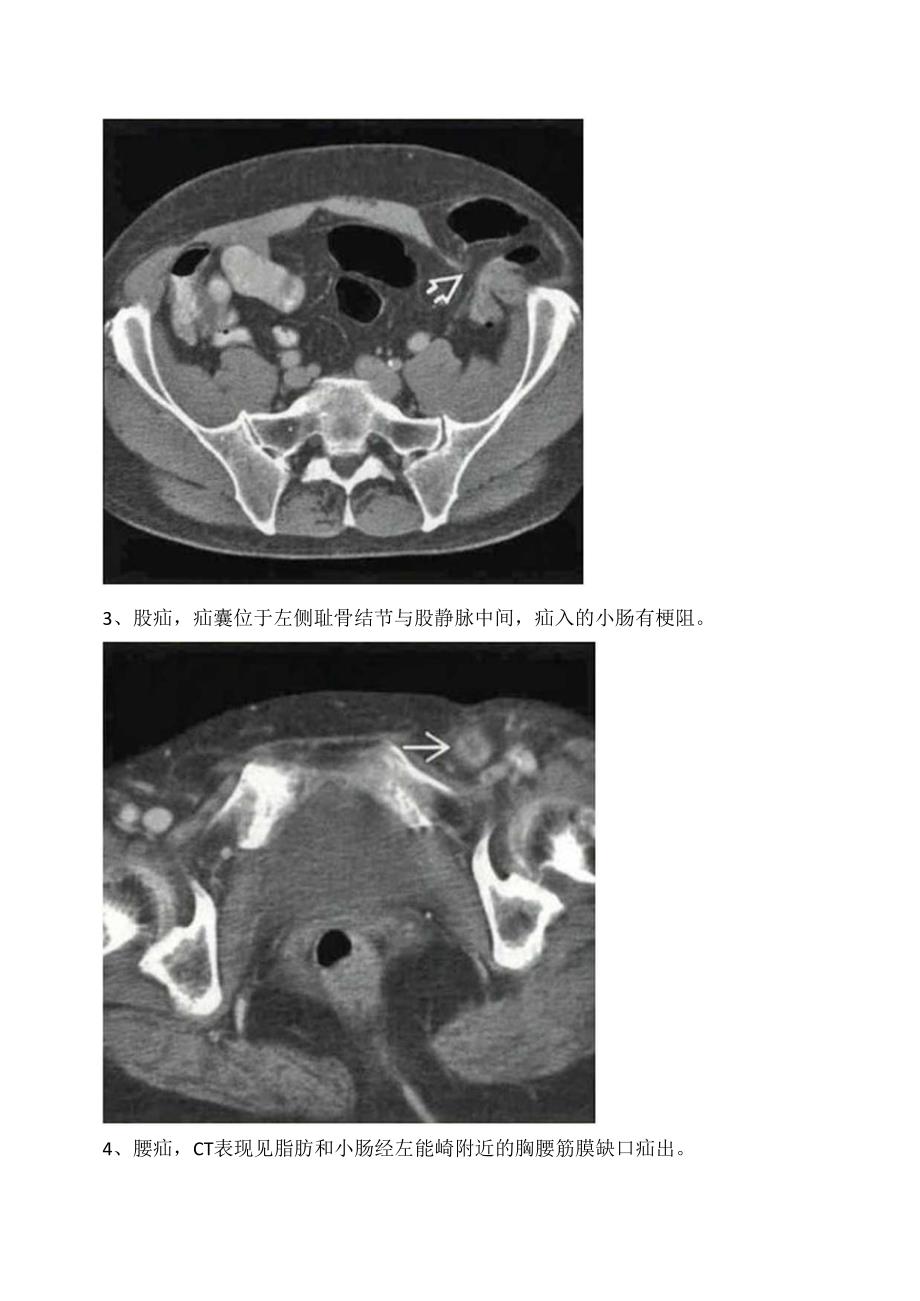

1、临床腹股沟疝、半月线疝、股疝等腹壁病变影像学CT表现1、腹股沟疝,右侧股管前方的疝囊,囊内可见含造影剂的小肠疝入,股静脉未见受压。2、半月线疝(斯皮格尔疝),结肠经左侧腹直肌旁的腹壁缺口疝出,贴附于腹外斜肌前方,疝囊完整。通常疝囊被腹斜肌腱膜覆盖。3、股疝,疝囊位于左侧耻骨结节与股静脉中间,疝入的小肠有梗阻。4、腰疝,CT表现见脂肪和小肠经左能崎附近的胸腰筋膜缺口疝出。5、皮脂腺囊肿,右臀部一包膜完整、水样密度病灶。6、腹壁血肿患者,右前下腹壁连接腹腔的透析导管,周围可见-闭块状高密度病灶。7、r宫内膜异位症,该病例为经历剖腹产的患者,腹壁切口周围一团块状软组织密度病灶,病灶部位周期性疼痛。8